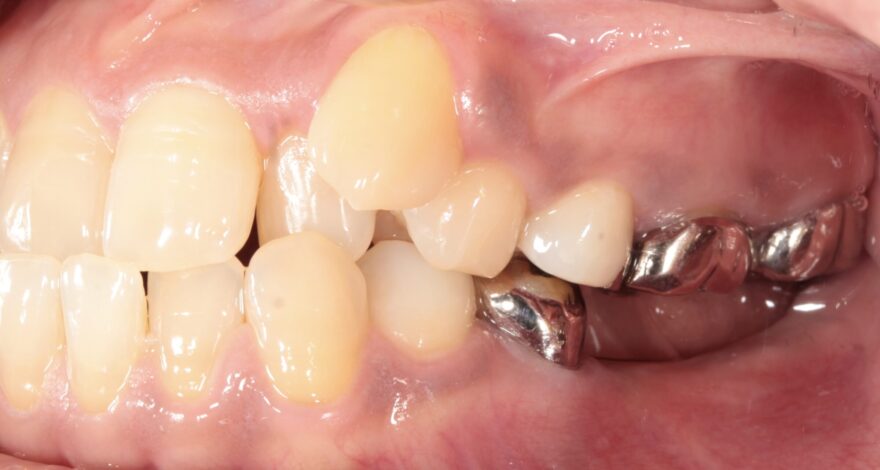

初診時の口腔内写真

左下の奥歯が崩壊しています。

右下の奥歯を失い、噛み合わせが歪んでいることが分かります。

治療中の口腔内写真

インプラント治療

奥歯用インプラント 440,000円×3本